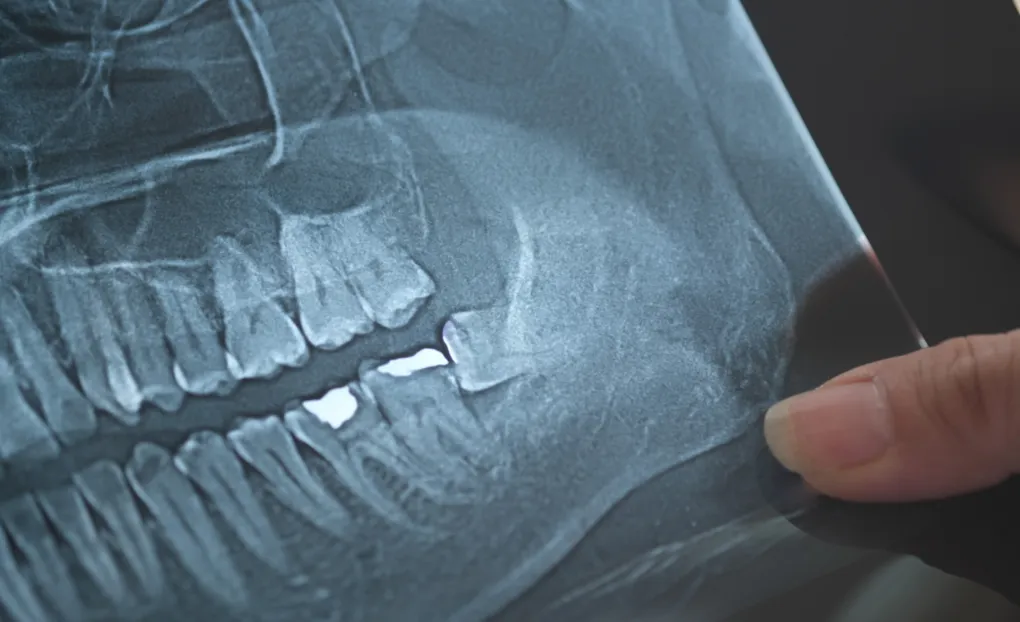

現在は痛みがなくても、将来的なトラブルを防ぐために抜歯する場合もあります。レントゲン撮影など精密検査を通じた総合的な判断が必要になりますので、親知らずが気になるようでしたら、一度当院までご相談ください。

- まっすぐに生えていて、周囲の歯や噛み合わせに影響しない場合には、必ずしも抜歯の必要はありません。ただし、歯肉の痛みや腫れが強い、親知らずが虫歯になっている場合には、早めの抜歯をおすすめします。抜歯については、レントゲンで状態を詳細に確認してから判断します。